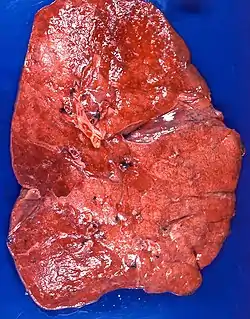

| Lipid pneumonia, exogenous Case 108 | |

The gross appearance of a lipid pneumonia is that in which there is an ill-defined, pale yellow area on the lung. This yellow appearance explains the colloquial term "golden" pneumonia.